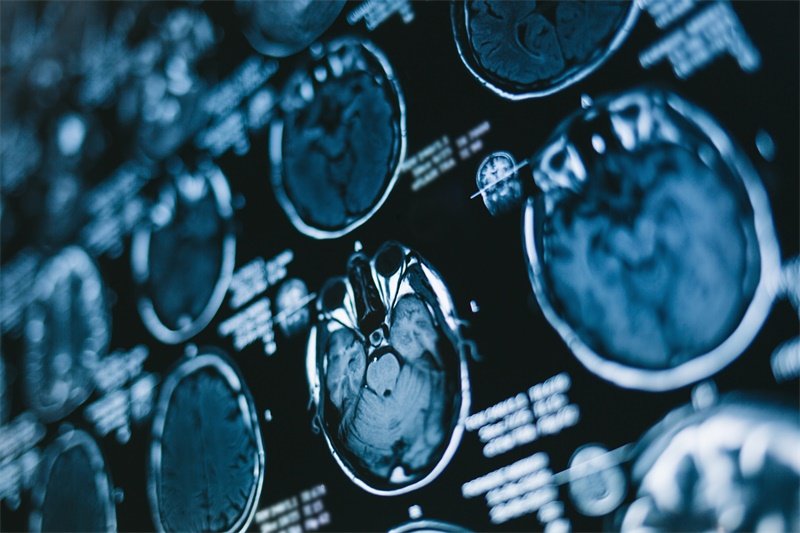

影像学检查:精准定位的关键

MRI是首选检查,可清晰显示肿瘤与神经根的关系——良性肿瘤多呈均匀强化的类圆形肿块,恶性肿瘤则表现为边界不清的混杂信号影。CT可评估椎间孔骨质破坏情况,X线片用于观察脊柱整体形态。对于疑似恶性肿瘤,需进一步行PET-CT排查全身转移。